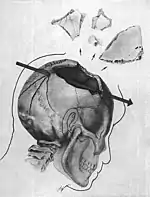

Parietal bone Trajectory of the missile through President Kennedy's skull. The bullet struck posterior part of his right parietal bone from behind.

Trajectory of the missile through President Kennedy's skull. The bullet struck posterior part of his right parietal bone from behind.